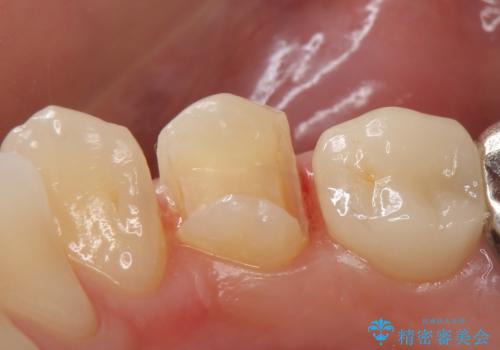

- 甘いものを食べると右下4番目の歯がしみるので診て欲しいといらっしゃった方の症例です。

古い銀歯と虫歯を除去後、PGA(ゴールド)インレーによる修復を行いました。